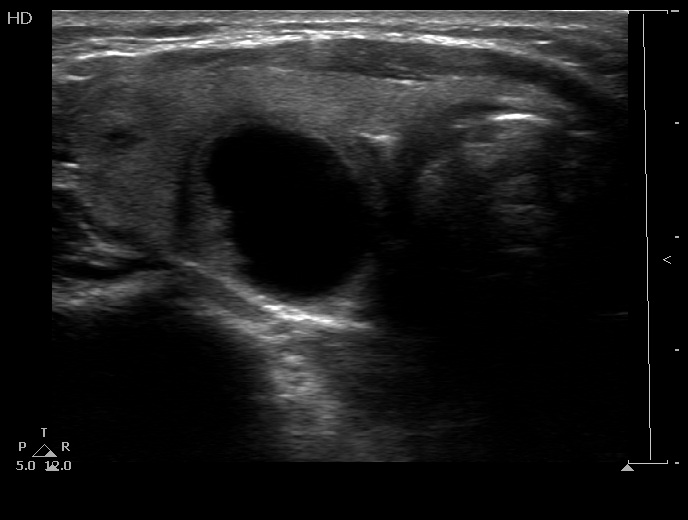

Intranodular hyperechogenic figures - case 367 (ultrasonographic picture 4)

Lower part of the right lobe, another trasnverse view. There is a small solid area in the lateral part of the nodule.